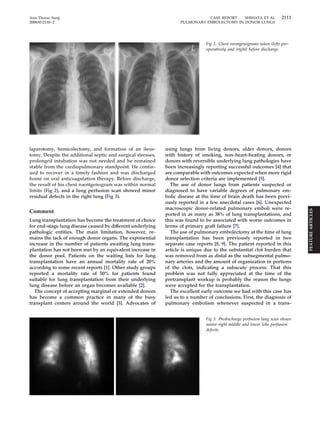

Fig 2. Chest roentgenograms taken (left) pre-operatively

and (right) before discharge.